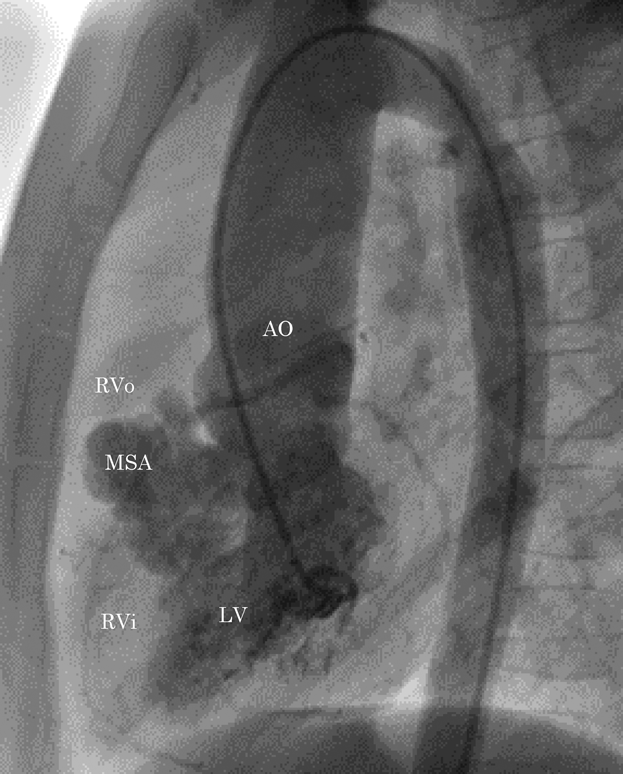

膜様部中隔瘤による右室流出路狭窄を呈した心室中隔欠損の一例Right Ventricular Outflow Obstruction by a Membranous Septal Aneurysm in a Ventricular Septal Defect